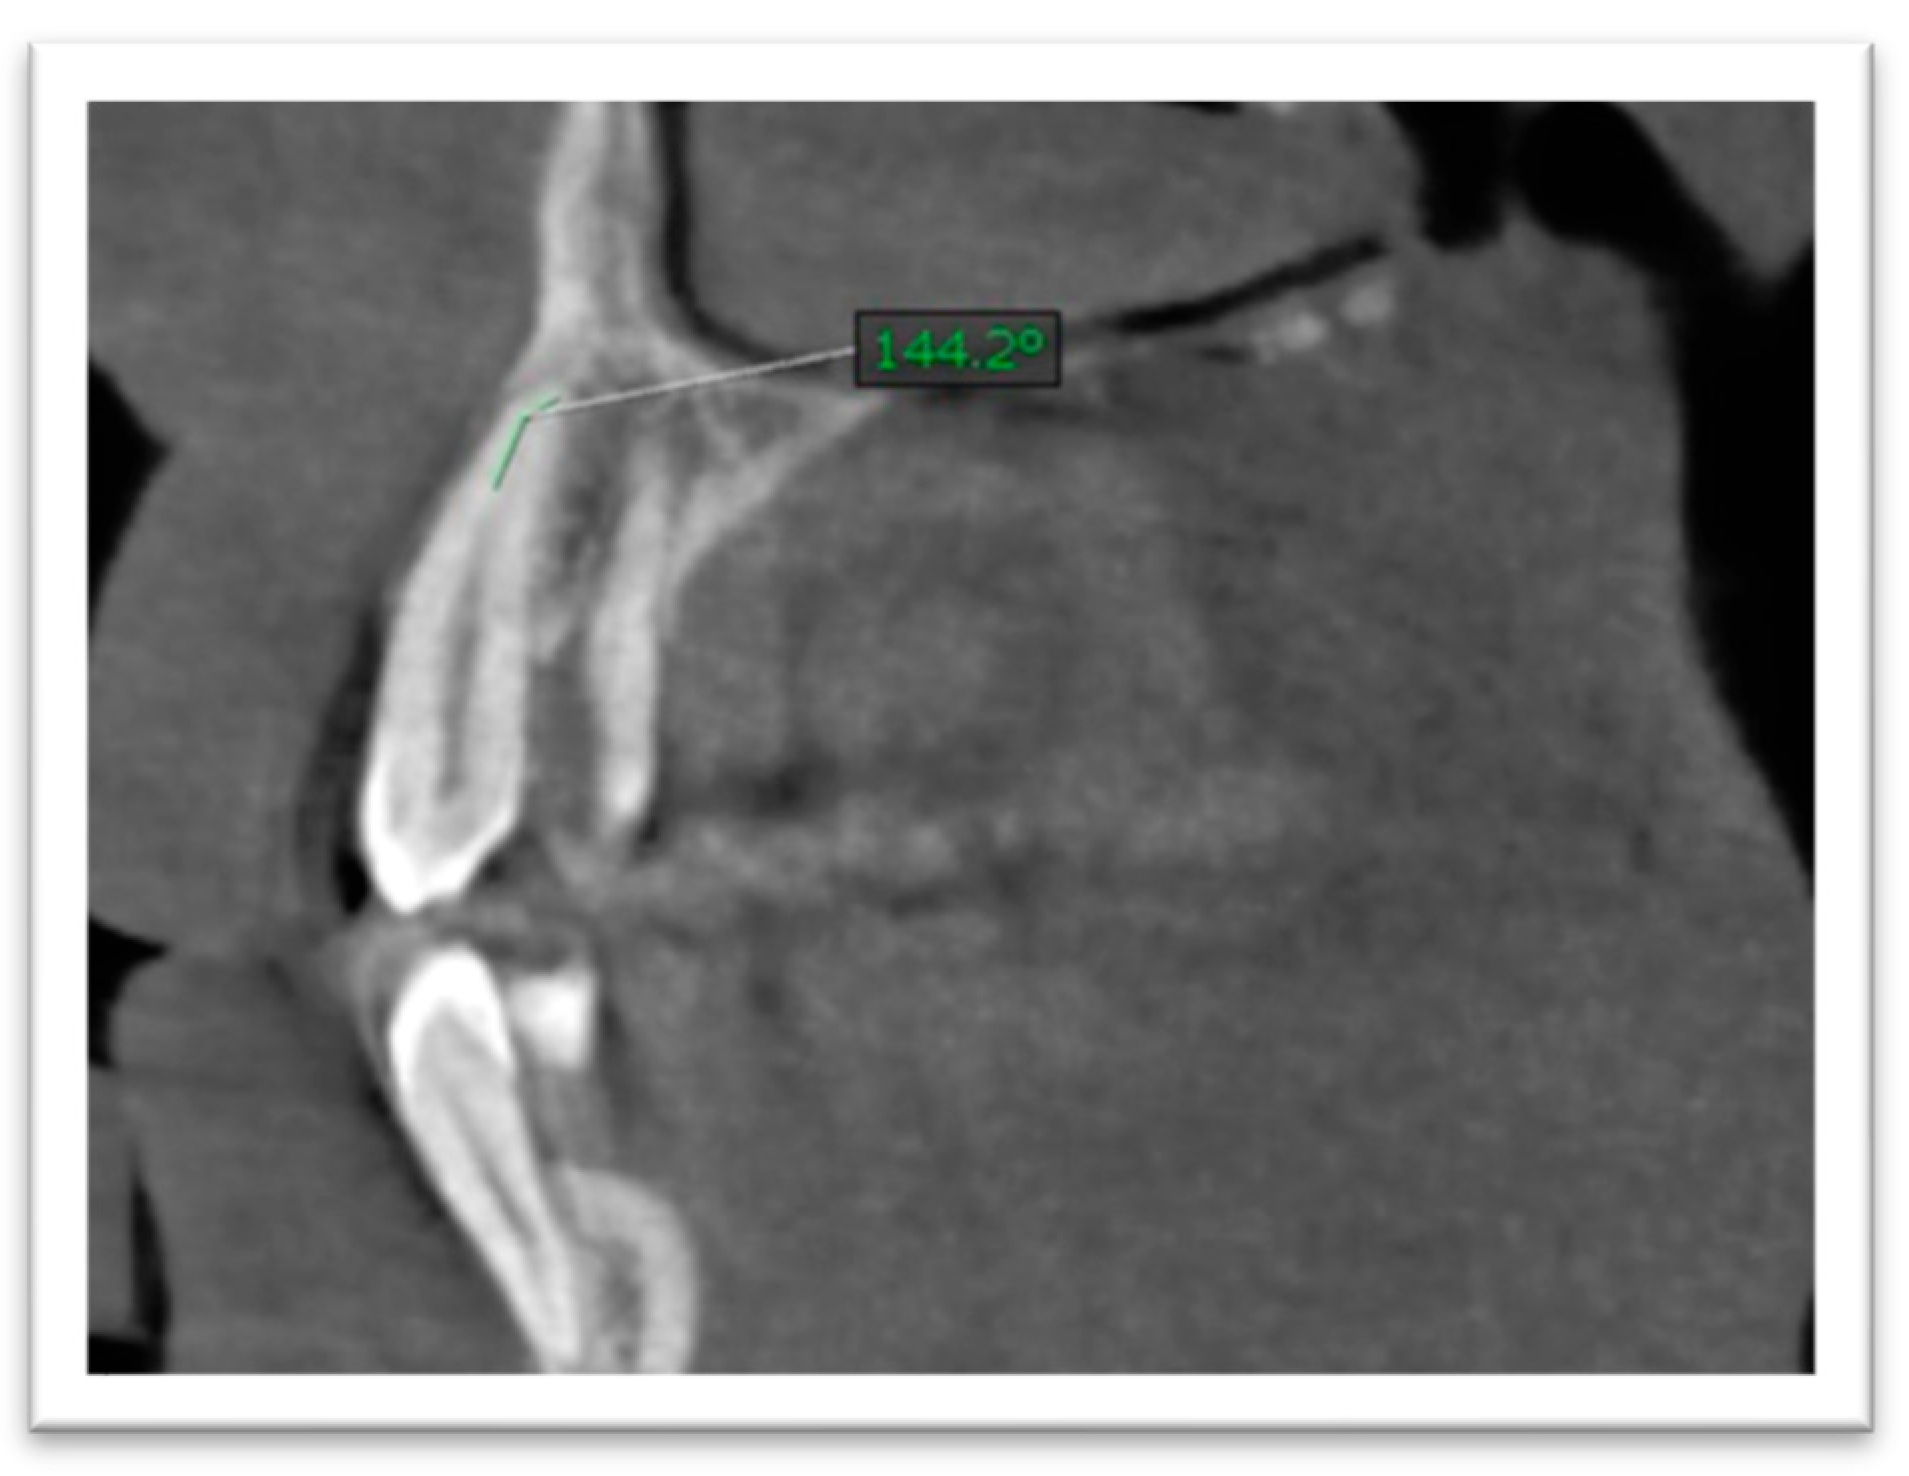

- Since root length was recorded as a straight-line distance, it may slightly underestimate true anatomic length in teeth with pronounced curvature; standardized reorientation was used to capture the maximum tooth length on the plane of measurement. Root canal curvature (angulation) was assessed by scrolling through sagittal and coronal planes. The curvature angle was measured using a Schneider-type approach: a first line was drawn parallel to the canal in the coronal third, and a second line was drawn from the point where the canal began to deviate to the apical foramen; the acute angle between these lines was recorded (Figure 4 and Figure 5). The curvature was categorized as mild (≤5°), moderate (5–20°), or severe (>20°) [22].